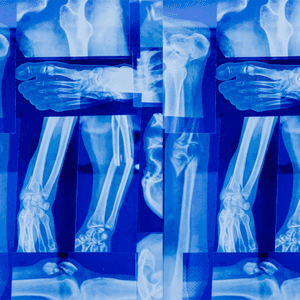

Terrible Triad Injury of the Elbow

Elbow. Information for professionalsWhat is a Terrible Triad Injury of the Elbow? A Terrible Triad Injury of the Elbow is a severe and complex injury that involves: Elbow Dislocation: The elbow bones are forced out of their normal positions. Radial Head or Neck Fracture: The radial head or neck, part of the radius bone near